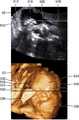

도 5는 일부 실시예에 따른, 초음파 진단 장치(1000)가 3 차원 초음파 영상 상에, 2 차원 초음파 영상이 나타내는 대상체의 단면의 위치를 나타내는 라인을 표시하는 예시를 도시한 도면이다.Fig. 5 is a diagram showing an example in which the ultrasonic

도 5를 참조하면, 초음파 진단 장치(1000)는 디스플레이 볼륨의 표면에 대응하는 2 차원 초음파 영상 내의 지점들(510) 중 사용자에 의해 선택된 3 차원 렌더링이 시작될 시작점의 깊이(500)와 동일한 깊이를 갖는 지점들을 상이한 깊이를 갖는 지점들과 구별하여 디스플레이할 수 있다.Referring to FIG. 5, the ultrasound

초음파 진단 장치(1000)는, 임신 중인 여성의 자궁의 단면을 나타내는 2 차원 초음파 영상(40)을 디스플레이할 수 있다. 2 차원 초음파 영상(40)에서 자궁벽, 태아, 태반은 밝은 영역으로, 양수는 어두운 영역으로 나타날 수 있다.The ultrasound

또한, 초음파 진단 장치(1000)는 3 차원 렌더링이 시작될 지점들(500)을 선택하는 사용자 입력을 수신할 수 있다. 3 차원 렌더링이 시작될 지점들(500)을 선택하는 사용자 입력은, 3 차원 렌더링이 시작될 시작점의 깊이를 선택하는 사용자 입력을 의미할 수 있다.The ultrasound

초음파 진단 장치(1000)는 선택된 지점들(500)에 기초하여 3 차원 초음파 영상(50)을 디스플레이할 수 있다. 3 차원 초음파 영상(50)은 자궁벽(532), 태아(534), 태아의 손(536) 및 태반(538)을 나타낼 수 있다. 또한, 초음파 진단 장치(1000)는 3 차원 초음파 영상(50)이 나타내는 디스플레이 볼륨의 표면의 위치를 2 차원 초음파 영상(40) 상에 라인(510) 형태로 디스플레이할 수 있다.The ultrasound

초음파 진단 장치(1000)는 3 차원 렌더링이 시작될 위치로써 선택된 지점들(500) 중 디스플레이 볼륨의 표면으로 렌더링된 지점들을 렌더링되지 않은 지점들과 구분하여 디스플레이할 수 있다.The ultrasound

예를 들어, 초음파 진단 장치(1000)는 2 차원 초음파 영상(40)에서 3 차원 렌더링이 시작될 위치로써 선택된 지점들(500) 중 자궁벽을 지나는 지점들(512), 태아의 손을 지나는 지점들(516) 또는 태반을 지나는 지점들(518)은, 디스플레이 볼륨의 표면으로 렌더링된 지점들일 수 있으며, 나머지 지점들은 양수를 지나는 지점들이기 때문에 디스플레이 볼륨의 표면으로 렌더링되지 않은 지점들일 수 있다.For example, the ultrasound

이에 따라, 초음파 진단 장치(1000)는 디스플레이 볼륨의 표면의 위치를 나타내는 지점들(510) 중 자궁벽을 지나는 지점들(512), 태아의 손을 지나는 지점들(516) 또는 태반을 지나는 지점들(518)에 대응되는 지점들은 실선으로 표현하고, 양수를 지나는 지점들에 대응되는 지점들은 점선으로 표현할 수 있다.Accordingly, the ultrasound

또한, 도 5에 도시되지 않았으나, 초음파 진단 장치(1000)는 3 차원 렌더링이 시작될 위치로써 선택된 지점들(500) 중 자궁벽을 지나는 지점들(512), 태아의 손을 지나는 지점들(516) 또는 태반을 지나는 지점들(518)은 실선으로 나타내고, 양수를 지나는 지점들을 점선으로 나타낼 수도 있다.Although not shown in FIG. 5, the ultrasound

초음파 진단 장치(1000)는 3 차원 초음파 영상(50) 상에, 2 차원 초음파 영상(40)이 나타내는 대상체의 단면의 위치를 라인(530) 형태로 디스플레이할 수 있다.The ultrasonic

또한, 도 5를 참조하면, 초음파 진단 장치(1000)는, 2 차원 초음파 영상이 나타내는 대상체의 단면에 대응하는 3 차원 초음파 영상 내의 지점들(530) 중 각각의 지점에서의 디스플레이 볼륨의 표면의 깊이가 사용자에 의해 선택된 3 차원 렌더링이 시작될 시작점의 깊이(500)와 동일한 깊이를 갖는 지점들을 상이한 깊이를 갖는 지점들과 구별하여 디스플레이할 수 있다.5, the ultrasound

예를 들어, 3 차원 초음파 영상(50) 내에서 대상체의 단면의 위치를 나타내는 지점들(530) 중 자궁벽을 지나는 지점들(512), 태아의 손을 지나는 지점들(516) 또는 태반을 지나는 지점들(518)은 각각의 지점에서 표현되는 디스플레이 볼륨의 표면의 깊이가 2 차원 초음파 영상(40)에서 선택된 렌더링 시작점(500)의 깊이와 동일하다. 그러나, 대상체의 단면의 위치를 나타내는 지점들(530) 중 나머지 지점들은, 대응되는 렌더링 시작점(500)이 양수를 나타내는 지점이므로, 디스플레이 볼륨의 표면의 깊이가 렌더링 시작점(500)의 깊이보다 더 깊다.For example, in the three-

따라서, 초음파 진단 장치(1000)는, 대상체의 단면의 위치를 나타내는 지점들(530) 중 자궁벽을 지나는 지점들(512), 태아의 손을 지나는 지점들(516) 또는 태반을 지나는 지점들(518)은 실선으로 나타내고, 나머지 지점들을 점선으로 나타낼 수 있다.

도 6은 일부 실시예에 따른, 3 차원 초음파 영상 상에 나타난 디스플레이 볼륨의 깊이가 조절됨에 따라, 초음파 진단 장치(1000)가 디스플레이 볼륨의 표면의 위치를 2 차원 초음파 영상 상에 나타내는 예시를 도시한 도면이다.6 illustrates an example in which the ultrasonic

도 6을 참조하면, 초음파 진단 장치(1000)는, 조절된 디스플레이 볼륨의 표면의 위치를 2 차원 초음파 영상 상에 나타낼 수 있다.Referring to FIG. 6, the ultrasound

도 5에서, 3 차원 초음파 영상(50)에 디스플레이된 태아(534)는 자신의 눈을 손(536)으로 가리고 있을 수 있다. 사용자는 태아(534)의 손(536)이 제거된 태아(534)의 얼굴을 디스플레이 볼륨으로 나타내기 위해, 태아(534)의 손(536) 영역에 대하여 3 차원 렌더링 파라미터를 조절함으로써, 태아(534)의 손(536) 영역을 깎아낼 수 있다.In FIG. 5, the

도 6에 도시된 2 차원 초음파 영상은 도 5에 도시된 2 차원 초음파 영상이며, 도 6에 도시된 3 차원 초음파 영상들은 도 5에 도시된 3 차원 초음파 영상(50)에서, 태아의 손(536) 영역이 깎아지는 정도에 따라, 디스플레이 볼륨의 표면이 변경된 영상들이다.The two-dimensional ultrasound image shown in FIG. 6 is the two-dimensional ultrasound image shown in FIG. 5, and the three-dimensional ultrasound images shown in FIG. 6 are obtained from the three-

도 6(a)는 태아(534)의 손(536)이 덜 제거된 경우를 나타내며, 도 6(b)는 태아(534)의 손(536)뿐만 아니라 태아(534)의 손(536)이 가리고 있던 태아(534)의 눈까지 제거된 경우를 나타내며, 도 6(c)는 태아(534)의 손(536)이 적당히 제거된 경우를 나타낸다.6 (a) shows a case where the

도 6(a)에 도시된 태아(534)의 손(536)이 덜 제거된 3 차원 초음파 영상(52)은 태아(534)의 얼굴뿐만 아니라 덜 제거된 태아(534)의 손(536)이 태아(534)의 얼굴에 붙어 있는 디스플레이 볼륨을 표현할 수 있다. 도 6(b)에 도시된 태아(534)의 눈까지 제거된 3 차원 초음파 영상(54)은 태아(534)의 눈의 일 부 영역까지 제거된 디스플레이 볼륨을 표현할 수 있다. 도 6(c)에서 도시된 태아(534)의 손(536)이 적당히 제거된 3 차원 초음파 영상(56)은 태아(534)의 얼굴 영역을 나타내는 디스플레이 볼륨을 표현할 수 있다.The

3 차원 초음파 영상(50) 내의 디스플레이 볼륨의 깊이가 변경됨에 따라, 초음파 진단 장치(1000)는, 2 차원 초음파 영상(40) 상에 디스플레이된 디스플레이 볼륨의 표면의 위치를 변경할 수 있다. 도 6에 도시된 바와 같이, 태아(534)의 손(536)이 제거될수록, 초음파 진단 장치(1000)는 디스플레이 볼륨의 표면에 대응되는 지점들의 위치를 아래로 변경할 수 있다.As the depth of the display volume in the

도 6에 도시된 2 차원 초음파 영상(40)들에 디스플레이된, 디스플레이 볼륨의 표면을 나타내는 라인의 위치를 비교하면, 태아(534)의 손(536)이 적당히 제거된 도 6(c)의 라인(526)의 형태는, 태아(534)의 손(536)이 덜 제거된 도 6(a)의 라인(522)의 형태 보다 깊게 패인 형태일 수 있다. 또한, 태아(534)의 손(536)이 적당히 제거된 도 6(c)의 라인(526)의 형태는, 태아(534)의 눈까지 제거된 도 6(b)의 라인(524)의 형태 보다 덜 패인 형태일 수 있다.6, the position of the line representing the surface of the display volume displayed on the two-

사용자는 2 차원 초음파 영상 상에 디스플레이된 디스플레이 볼륨의 표면에 대응되는 지점들의 위치를 확인함으로써, 디스플레이 볼륨 중 일부를 삭제하거나 되살릴 수 있다.